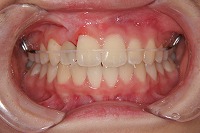

正面 | ![]() |

![]() |

反対咬合を主訴に来院された、右側唇顎裂の10歳6ヵ月の女の子です。診断「右側唇顎口蓋裂で反対咬合を伴う」1期治療で反対咬合の解消と上顎の前歯の並びを修正しました。2期治療は抜歯をせず治療を行いました。